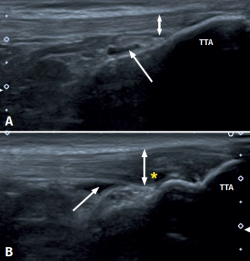

Figure 3. Ultrasound view of proximal patellar tendinopathy with linear probe in craniocaudal longitudinal panoramic view (from left to right). Note the area of decreased echogenicity (hypoechoic), marked with an asterisk, loss of the fibrillar pattern in the deepest and proximal region of the tendon secondary to disruption of the collagen bands, and anteroposterior 8.5 mm thickening (double arrow). ATT: anterior tibial tuberosity.

The ultrasound study of a damaged tendon evidences hypoechogenicity and loss of the fibrillar pattern, the appearance of disorganised connective tissue, and thickening of the tendon (Figure 3). In some cases we observe well delimited hypoechoic images indicating intra-substance rupture with nodular or fibrillar shapes, commonly manifesting in the deepest zone of the tendon in the lower pole adjacent to the patella (Figure 4).

Figure 4. High-resolution ultrasound study of patellar tendinopathy. Linear probe with longitudinal view. The double arrow shows increased tendon thickness, with hypoechogenic altered fibrillar pattern (#), intra-substance rupture (asterisk) and fibrosis (arrow).

In the middle portion of the tendon we may observe thickening (> 3.5 mm) associated to hypoechoic areas with zones of disorganised collagen and loss of the fibrillar pattern.

It is also common to identify cortical irregularities in the proximal enthesis of the tendon at the point where it joins the patella, involvement of the paratendon and adherences to Hoffa's fat pad. Any calcifications will be seen as white hyperechogenic zones (Figure 5).